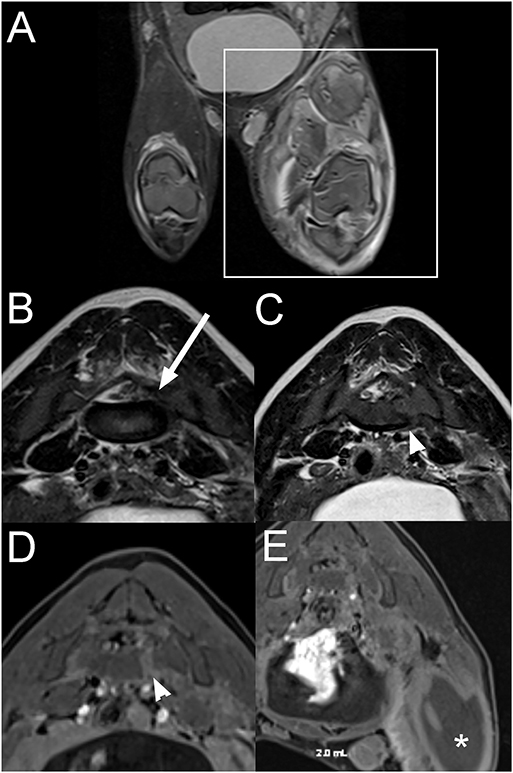

A 3-month-old female intact pig presented after being found recumbent on the side of the road. On presentation, the pig was dull and unable to stand. A wound previously closed with staples was present on the right pelvic limb, and the left pelvic limb appeared diffusely swollen. On neurological examination, the pig was non-ambulatory with moderate paresis, delayed proprioceptive placement, decreased patellar, and normal withdrawal reflexes in the right pelvic limb. There was complete monoplegia with absent patellar and withdrawal reflexes and absent superficial and deep nociception on the left pelvic limb. Lumbosacral pain was also noted on palpation. The rest of the neurological examination was unremarkable. The neurolocalisation was L4-S3 myelopathy. Differential diagnoses included a vertebral fracture or luxation with subsequent spinal cord or nerve injury, an epidural abscess, myositis involving the left pelvic limb, cellulitis, or an abscess in the proximal portion of the pelvic limb with secondary constrictive neuropathy and less likely rabies. Blood work was consistent with an inflammatory leukogram, muscle damage, and thrombocytopenia. Radiographs of the left pelvic limb revealed gas within the soft tissues surrounding the left femur, consistent with a penetrating wound but no evidence of a fracture. Thoracic radiographs were within normal limits. On MRI of the pelvis (Figure 7), there is a moderate amount of extradural material T2W and T1W hypointense to the spinal cord within the left side of the vertebral canal at the L6-S1 intervertebral disc space, extending caudally along S1 vertebrae and into the left S1-S2 intervertebral foramen. The nucleus pulposus of the lumbosacral intervertebral disc is smaller. Associated with the body of S1 vertebrae, there is a left parasagittal T2W hyperintense, T1W hypointense to hyperintense (to the bone) and moderately contrast enhancing line, and the ventral cortex of S1 vertebrae has a step defect. Most muscles of the left thigh, left iliopsoas, and caudal left epaxial muscles are swollen, heterogeneously T2W hyperintense and surrounded by fluid. On post-contrast images, the imaged muscle of the left thigh and the left iliopsoas muscle display large non-contrast enhancing areas surrounded by a rim of mild to moderate contrast-enhancement and mild contrast-enhancement of the surrounding muscles. The left inguinal lymph node is markedly enlarged with a rim of moderate contrast-enhancement. The spinal abnormalities were consistent with a fracture of S1 vertebra with associated epidural hemorrhage, lacerated sacral nerve roots, or a combination of both. The changes to the left pelvic limb, iliopsoas, and caudal left epaxial muscles were consistent with trauma, myositis and areas of muscle necrosis or abscessation. The regional lymphadenopathy was considered most likely reactive.

Figure 7. Dorsal STIR (A), transverse T2W (B,C), and transverse T1W post contrast fat suppressed (D,E) images of the pelvis and lumbosacral vertebral column in a 3-month-old pig with a L4-S3 myelopathy (Case 7). There is severe extensive swelling and STIR hyperintensity of the musculature of the left pelvic limb compared to normal muscle (A; within box) with large non-contrast enhancing areas surrounded by rim of contrast-enhancement (E; *). T2W hypointense to the spinal cord extradural material is present within the left side of the vertebral canal at the L6-S1 intervertebral disc space, extending into the left S1-S2 intervertebral foramen (B; arrow). There is a left parasagittal T2W hyperintense, T1W hypo- to hyperintense (to bone) and moderately contrast enhancing line associated with the body of the S1 vertebra with a step defect of the ventral cortex (C,D; arrowhead). The abnormalities were consistent with a fracture of the S1 vertebra with associated epidural hemorrhage, nerve root laceration, and left pelvic limbs muscle necrosis or abscessation.